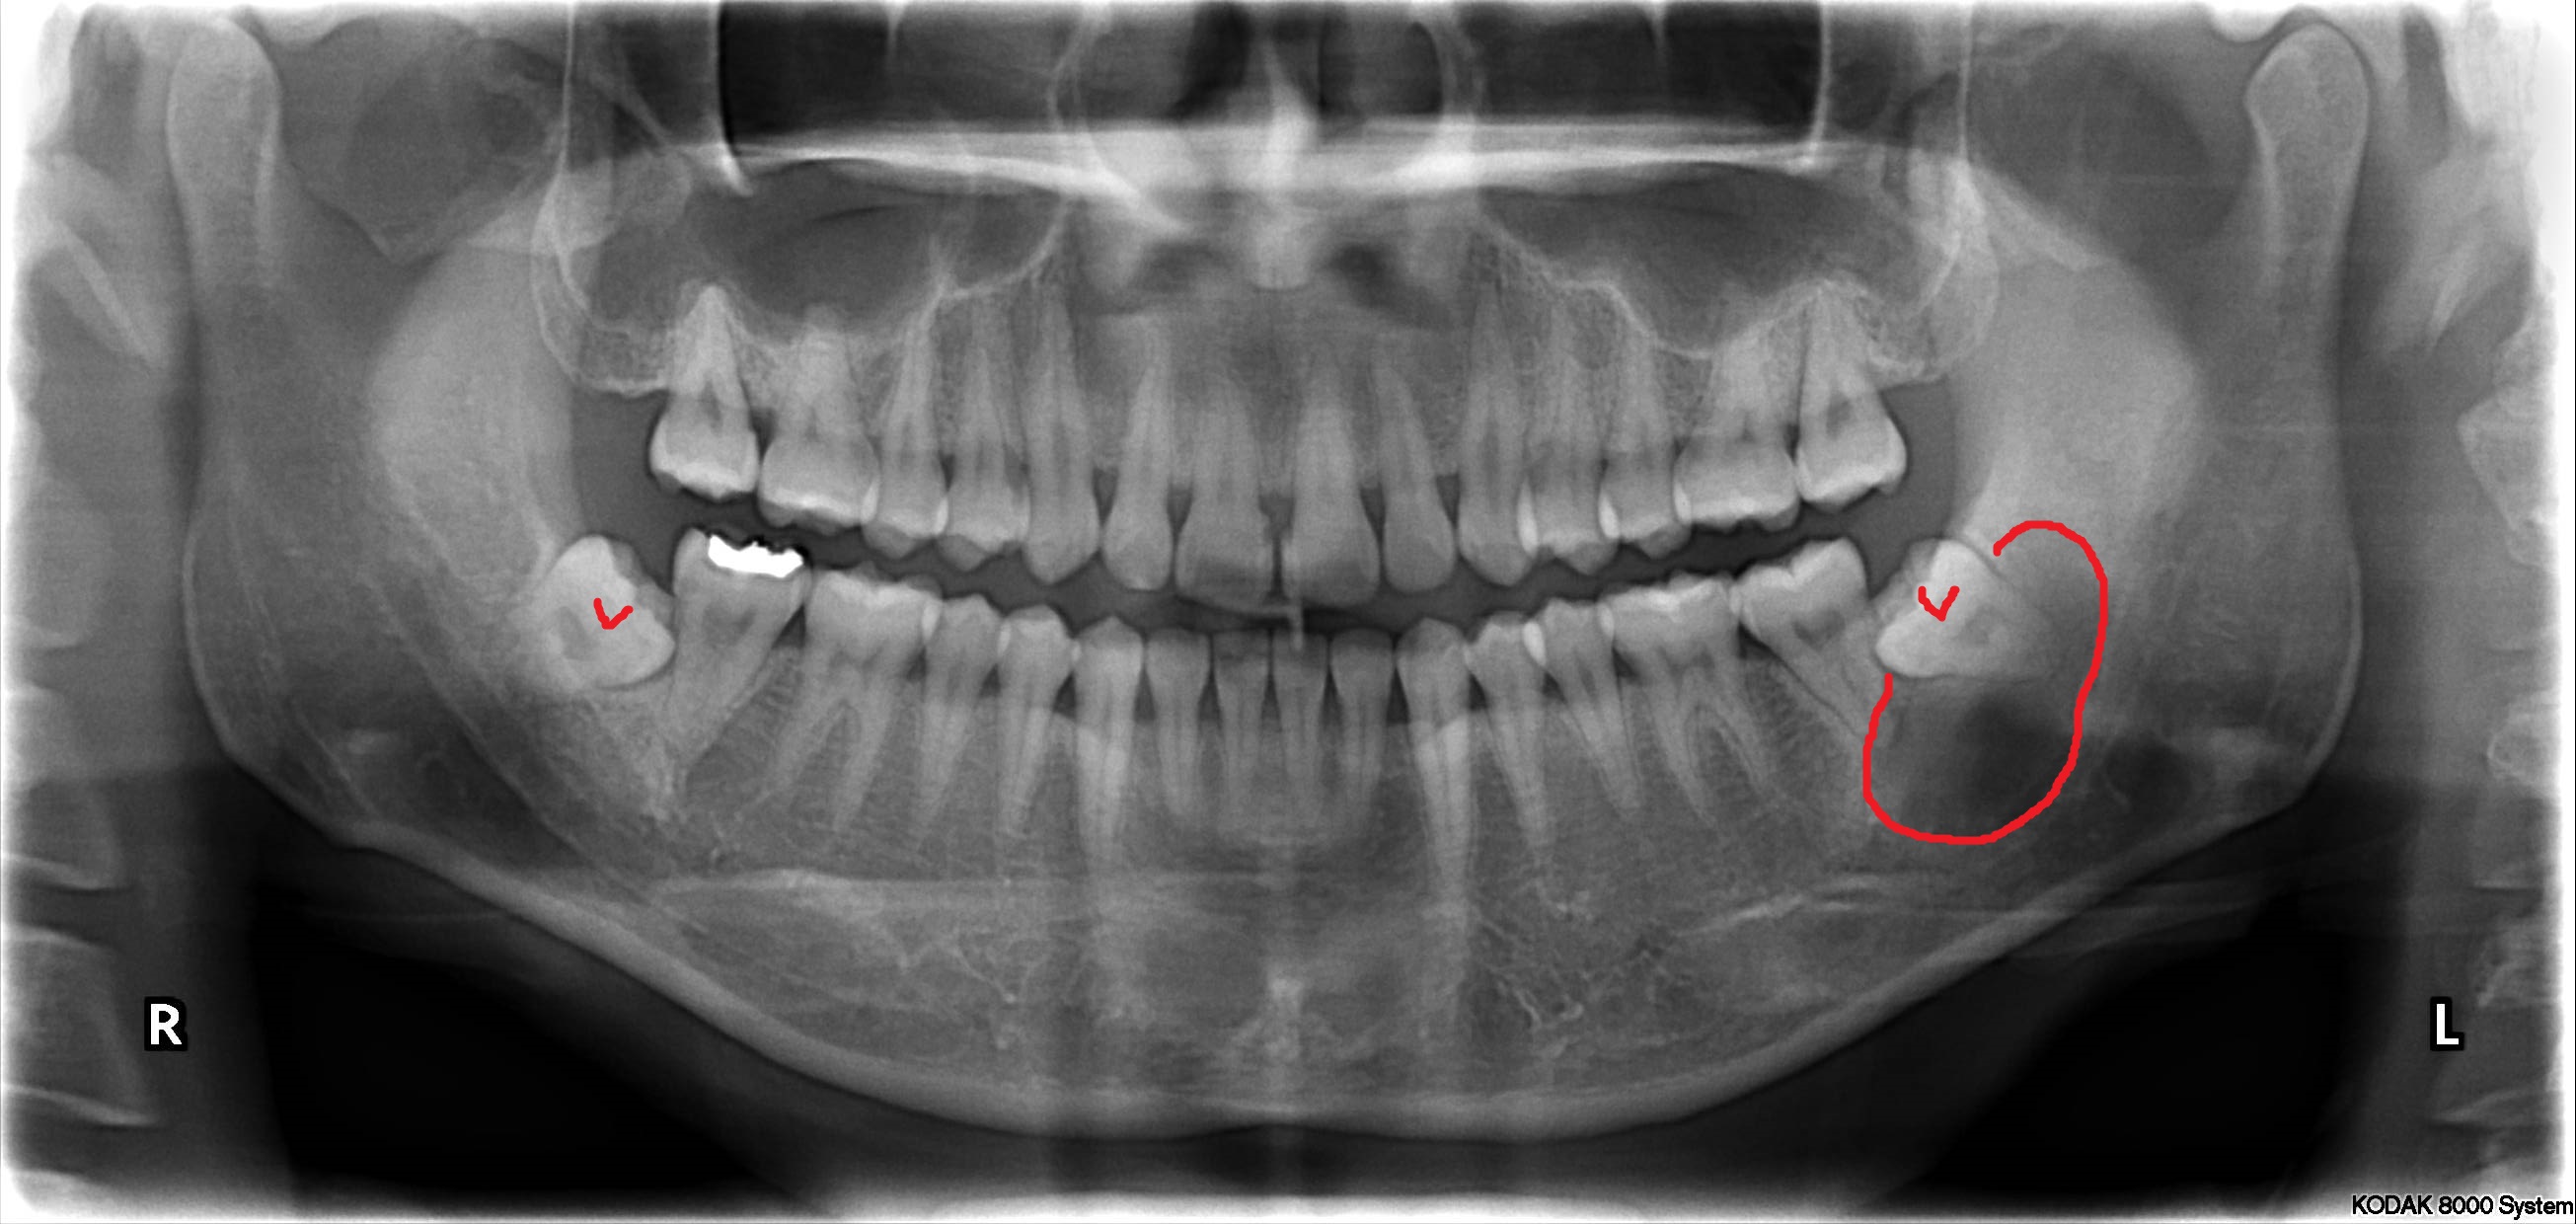

사랑니는 우리 입속에 가장 뒤에 난 어금니를 말하며, 전문용어로 설명해 드리면 제3대구치라고 하며 얼굴을 중심으로 좌우로 8번째 자리하고 있는 치아를 말합니다. 사랑니는 사춘기 이후에 자란다고 합니다. 사춘기에는 여러 가지 감정을 느끼게 되고 그 감정 중 하나가 사랑이라는 감정이지요. 그래서 이 치아를 사랑니라고 부른다고 합니다.

치과 치료를 하면 알 수 있는 것이 치아는 함부로 뽑지 않습니다. 정말 최대한 살려보고 그래도 안 되면 뽑아서 임플란트 등으로 빈자리를 채웁니다. 사랑니는 다른 치아들과 달리 발치를 해야 할 때도 있습니다. 잘 자란 사랑니는 특별한 문제를 일으키지 않아 뽑지 않아도 됩니다. 하지만 대부분의 사랑니는 말썽을 부립니다. 출혈, 염증, 통증 및 악취, 충치 들 여러 가지 문제를 일으킬 확률이 높기 때문에 뽑아야 합니다.